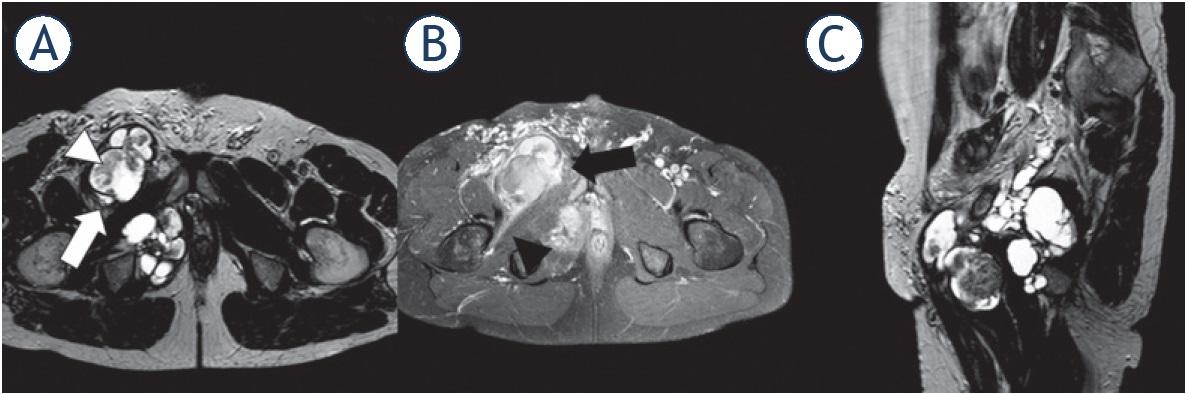

Figure 3

1.5-T MRI of the pelvis

![1.5-T MRI of the pelvis (A) proton density [PD] axial, (B) contrast-enhanced T1 fat saturation [FS] axial, (C) PD sagittal) of a 49-year-old patient. The higher-grade polycyclic/multilobulated sarcoma in the right pelvis (white arrow) shows heterogeneous contrast enhancement (black arrow), infiltrative behavior (black arrowhead), and solid components within cystic tissue (white arrowhead).](https://sciendo-parsed-data-feed.s3.eu-central-1.amazonaws.com/60724a50989a071a6405e20e/j_raon-2021-0007_fig_003.jpg?X-Amz-Algorithm=AWS4-HMAC-SHA256&X-Amz-Date=20220819T130336Z&X-Amz-SignedHeaders=host&X-Amz-Expires=18000&X-Amz-Credential=AKIA6AP2G7AKP25APDM2%2F20220819%2Feu-central-1%2Fs3%2Faws4_request&X-Amz-Signature=80c017f135646d168216ee1f41e05bd0548988111ace3d831b89814099a12e43)